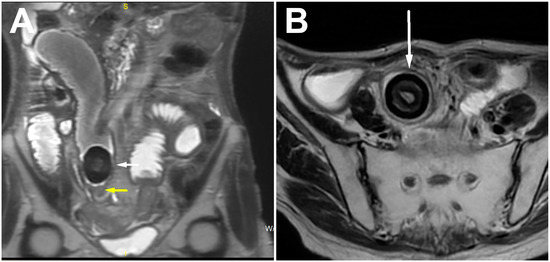

| Calcified bezoar (“Bezoar egg”) | Hyperechoic oval structure with posterior acoustic shadow within the bowel lumen | Oval, clearly demarcated mass with centrally placed gas | T1w and T2w hipointense oval mass with layered structure |